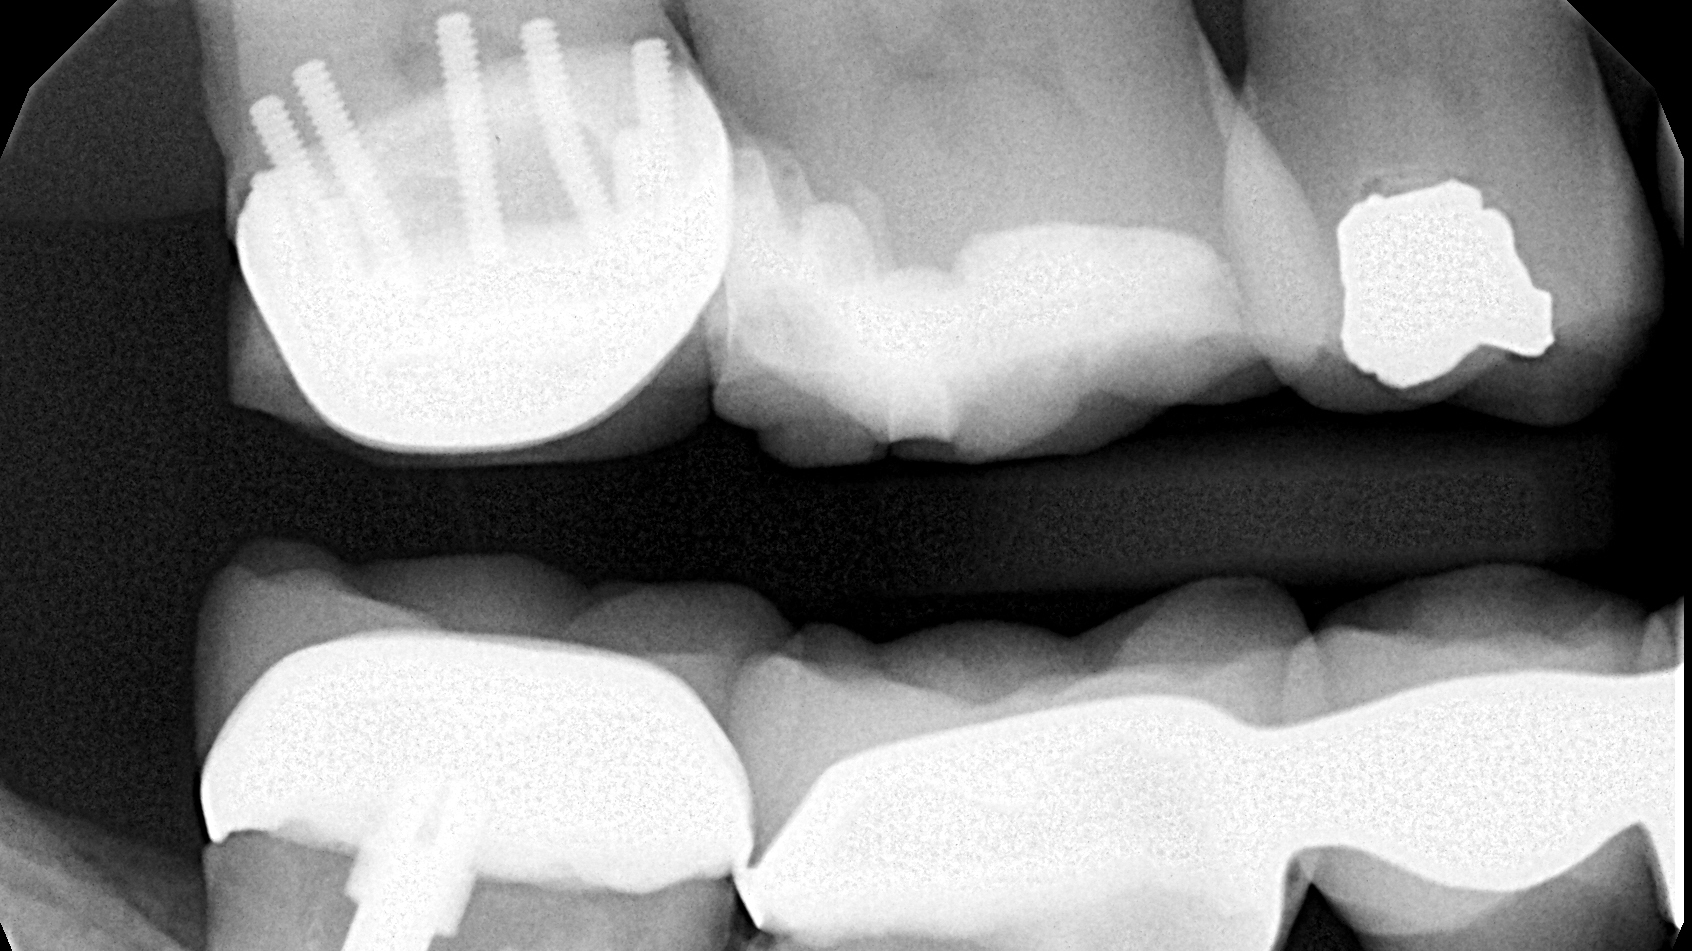

Dental Pin Adalah. Dengan pemahaman yang lebih baik tentang apa itu pasak gigi, proses pemasangannya, dan manfaat serta risikonya, anda dapat membuat keputusan yang tepat bersama dengan dokter gigi anda. Jika gigi tidak kunjung stabil, splint sementara akan diganti dengan splint permanen. Dental splinting permanen biasa digunakan untuk menangani gigi yang berpotensi semakin goyang. pasak gigi adalah solusi penting dalam perawatan gigi untuk memperkuat gigi yang melemah atau rusak. pasak gigi atau pins and posts adalah material tambahan yang digunakan sebagai penyangga pada proses restorasi. pins retain the restoration in position and and hold the restoration and prepared tooth structure together and they. crown gigi, atau biasa disebut sebagai mahkota gigi, adalah salah satu bentuk restorasi gigi yang menutupi seluruh gigi, gigi dengan pasak, atau. pasak gigi atau juga disebut dental pin & post, merupakan salah satu jenis penunjang gigi yang digunakan pada gigi yang sudah melalui perawatan. a dental pin, also known as a tooth pin, is a small post typically made of metal, ceramic, or composite material that. Metode ini biasa digunakan selama dua minggu sampai maksimal dua bulan. splinting gigi atau dental splinting, merupakan tindakan medis non invasif (tanpa pembedahan) yang dilakukan untuk merekatkan gigi yang lemah.

Jika gigi tidak kunjung stabil, splint sementara akan diganti dengan splint permanen. Dental splinting permanen biasa digunakan untuk menangani gigi yang berpotensi semakin goyang. splinting gigi atau dental splinting, merupakan tindakan medis non invasif (tanpa pembedahan) yang dilakukan untuk merekatkan gigi yang lemah. pasak gigi atau juga disebut dental pin & post, merupakan salah satu jenis penunjang gigi yang digunakan pada gigi yang sudah melalui perawatan. Metode ini biasa digunakan selama dua minggu sampai maksimal dua bulan. a dental pin, also known as a tooth pin, is a small post typically made of metal, ceramic, or composite material that. pasak gigi atau pins and posts adalah material tambahan yang digunakan sebagai penyangga pada proses restorasi. pins retain the restoration in position and and hold the restoration and prepared tooth structure together and they. pasak gigi adalah solusi penting dalam perawatan gigi untuk memperkuat gigi yang melemah atau rusak. crown gigi, atau biasa disebut sebagai mahkota gigi, adalah salah satu bentuk restorasi gigi yang menutupi seluruh gigi, gigi dengan pasak, atau.